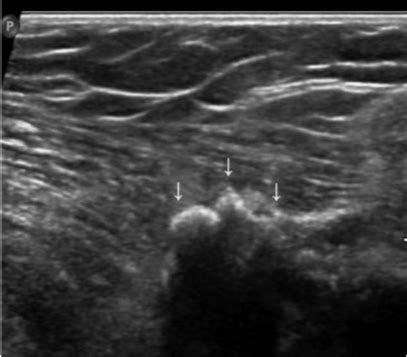

腋下淋巴结肿大怎么办

一般来讲,淋巴结轻度肿大,单个或散在的几个,质软,无压痛,无粘连,无伴有其他症状,可暂时不必治疗,但必须密切观察其变化。如不增大或逐渐缩小,则可继续观察;如果增大或增多,必须找医生诊治。如果肿大的淋巴结较大、较多,尤其是成串,逐渐增大或迅速增大,与周围组织粘连,其他部位(如腋下)也有淋巴结肿大,伴有发热、贫血、消瘦等其他症状者,都应该立即到医院做相关检查(甚至淋巴结活检),以达到及时诊断和治疗。 预防措施 1、养成良好的生活习惯。 2、保持良好的心态,稳定的情绪,拥有健康的饮食习惯,平时多吃水果蔬菜等,提高自我免疫力。 3、必须在重油烟处工作的人,尽量保护好自己,比如戴上口罩,定时出去呼吸一些新鲜空气,每年起码做一次检查等。 4、.远离烟雾、酒精、药物、辐射、农药、噪音、挥发性有害气体、有毒有害重金属等。